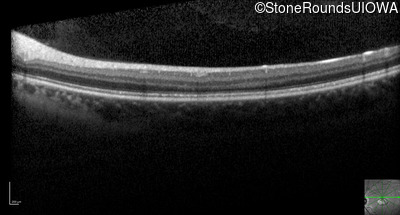

Optical Coherence Tomography - Right - 20/32 sc

Exemplar / OCT Stack